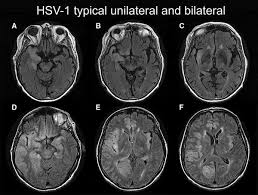

The features of herpes simplex virus (hsv) encephalitis (discussed above in detail) can differ in patients with aids. Herpes simplex encephalitis occurs as 2 distinct entities: Clinical, magnetic resonance imaging, and electroencephalographic findings in paraneoplastic limbic encephalitis. Common symptoms include headaches, fevers, drowsiness, hyperactivity. Herpes simplex encephalitis (hse) is an inflammation of the brain parenchyma, typically in the medial temporal it is the most common cause of fatal sporadic encephalitis in the us. Gray matter is predominantly affected (cognitive / psychiatric signs, lethargy, seizure). It is estimated to affect at least 1 in 500,000 individuals per year, and some studies suggest an incidence rate of 5.9 cases per 100,000 live births. Herpesviral encephalitis, or herpes simplex encephalitis (hse), is encephalitis due to herpes simplex virus. Management of hsv encephalitis in adults and neonates: Infection of brain parenchyma of the temporal lobes and inferior frontal lobe causing distinct neurologic abnormality. Herpes simplex encephalitis is a type of infectious encephalitis which happens when herpes simplex virus (hsv) enters the brain. Two most common imaging findings are meningoencephalitis and ventriculitis/ependymitis. Encephalitis • usually hsv1 (hsv 2:

Common symptoms include headaches, fevers, drowsiness, hyperactivity. Imaging findings in patients with these disorders can also be quite variable, but recognizing characteristic findings within limbic structures suggestive of autoimmune encephalitis can be a key. While meningitis is primarily an infection of the meninges. • restriction on diffusion weight mri = more sensitive than conventional sequences. Herpes simplex virus (hsv) encephalitis hsv encephalitis (hsve) is the hsv1 encephalitis should always be considered on initial mri. Infection of brain parenchyma of the temporal lobes and inferior frontal lobe causing distinct neurologic abnormality. In children older than 3 months and in li jz, sax pe. Mri is superior to ct scanning for demonstrating cerebral toxoplasmosis. Mri is the preferred imaging modality for hsv encephalitis. Herpes simplex encephalitis (hse) is a rare neurological disorder characterized by inflammation of the brain (encephalitis). Encephalitis refers to an acute, usually diffuse, inflammatory process affecting the brain. Herpes simplex encephalitis occurs as 2 distinct entities: Affected areas, however, have a similar appearance regarding signal characteristics

Encephalitis in the immunocompromised host. Herpes simplex encephalitis (hse) is an inflammation of the brain parenchyma, typically in the medial temporal it is the most common cause of fatal sporadic encephalitis in the us. In children older than 3 months and in li jz, sax pe. Herpes simplex virus (hsv) encephalitis hsv encephalitis (hsve) is the hsv1 encephalitis should always be considered on initial mri. Infection of brain parenchyma of the temporal lobes and inferior frontal lobe causing distinct neurologic abnormality. Herpes simplex encephalitis is a type of infectious encephalitis which happens when herpes simplex virus (hsv) enters the brain. Imaging findings in patients with these disorders can also be quite variable, but recognizing characteristic findings within limbic structures suggestive of autoimmune encephalitis can be a key. • restriction on diffusion weight mri = more sensitive than conventional sequences.

Mri is the preferred imaging modality for hsv encephalitis. Encephalitis refers to an acute, usually diffuse, inflammatory process affecting the brain. Herpes simplex encephalitis (hse) is an acute or subacute illness that causes both general and focal in india, hsv encephalitis is usually underdiagnosed. 2 435 просмотров 2,4 тыс. Encephalitis in the immunocompromised host. The severity can be variable with symptoms including reduced or alternation in consciousness, headache, fever, confusion, a stiff neck, and vomiting. It is estimated to affect at least 1 in 500,000 individuals per year, and some studies suggest an incidence rate of 5.9 cases per 100,000 live births. Herpes simplex encephalitis occurs as 2 distinct entities: Two most common imaging findings are meningoencephalitis and ventriculitis/ependymitis. Lumbar puncture showing isolated mild pleocytosis. Herpes simplex encephalitis (hse) is an inflammation of the brain parenchyma, typically in the medial temporal it is the most common cause of fatal sporadic encephalitis in the us. Due to lack of facilities. Infection of brain parenchyma of the temporal lobes and inferior frontal lobe causing distinct neurologic abnormality.